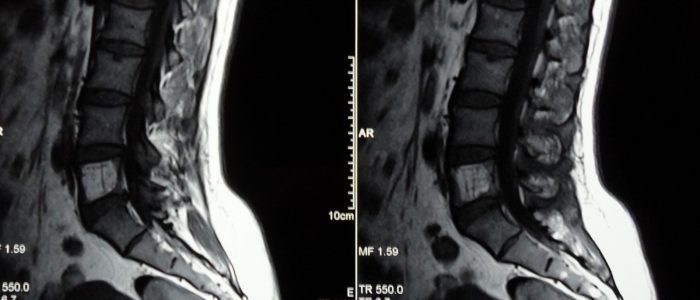

Исследование гемангиомы позвоночника чаще проходит посредством МРТ и УЗИ.

Перед тем, как начать лечение гемангиомы, важно поставить окончательный диагноз и подтвердить заболевание. Для этого больного отправляют на диагностическое исследование, которое покажет, насколько изменилось состояние позвоночника, каких размеров новообразование, какова его природа, и определит наличие или отсутствие метастаз. При гемангиоме проводят такие диагностические исследования:

- рентгенография;

- компьютерная томография;

- магнитно-резонансная томография;

- исследование сосудов позвоночника при помощи рентгенографического метода, с применением контраста.

Гемангиома тела позвонка на МРТ или КТ будет выглядеть как округлое, мягкое новообразование, которое имеет свои размеры и положение относительно позвоночника. Если опухоль переродилась в злокачественное новообразование, доктор оценит степень поражения метастазами соседних органов, а также рядом расположенных межпозвоночных отделов. Злокачественная гемангиома на КТ покажет, что трабекулярные полости не заполнены липидами, при этом присутствует мягкотканная солидная часть новообразования. Сама трабекулярная структура характеризуется неравномерностью, поражено не только тело позвонка, но и его дужки.